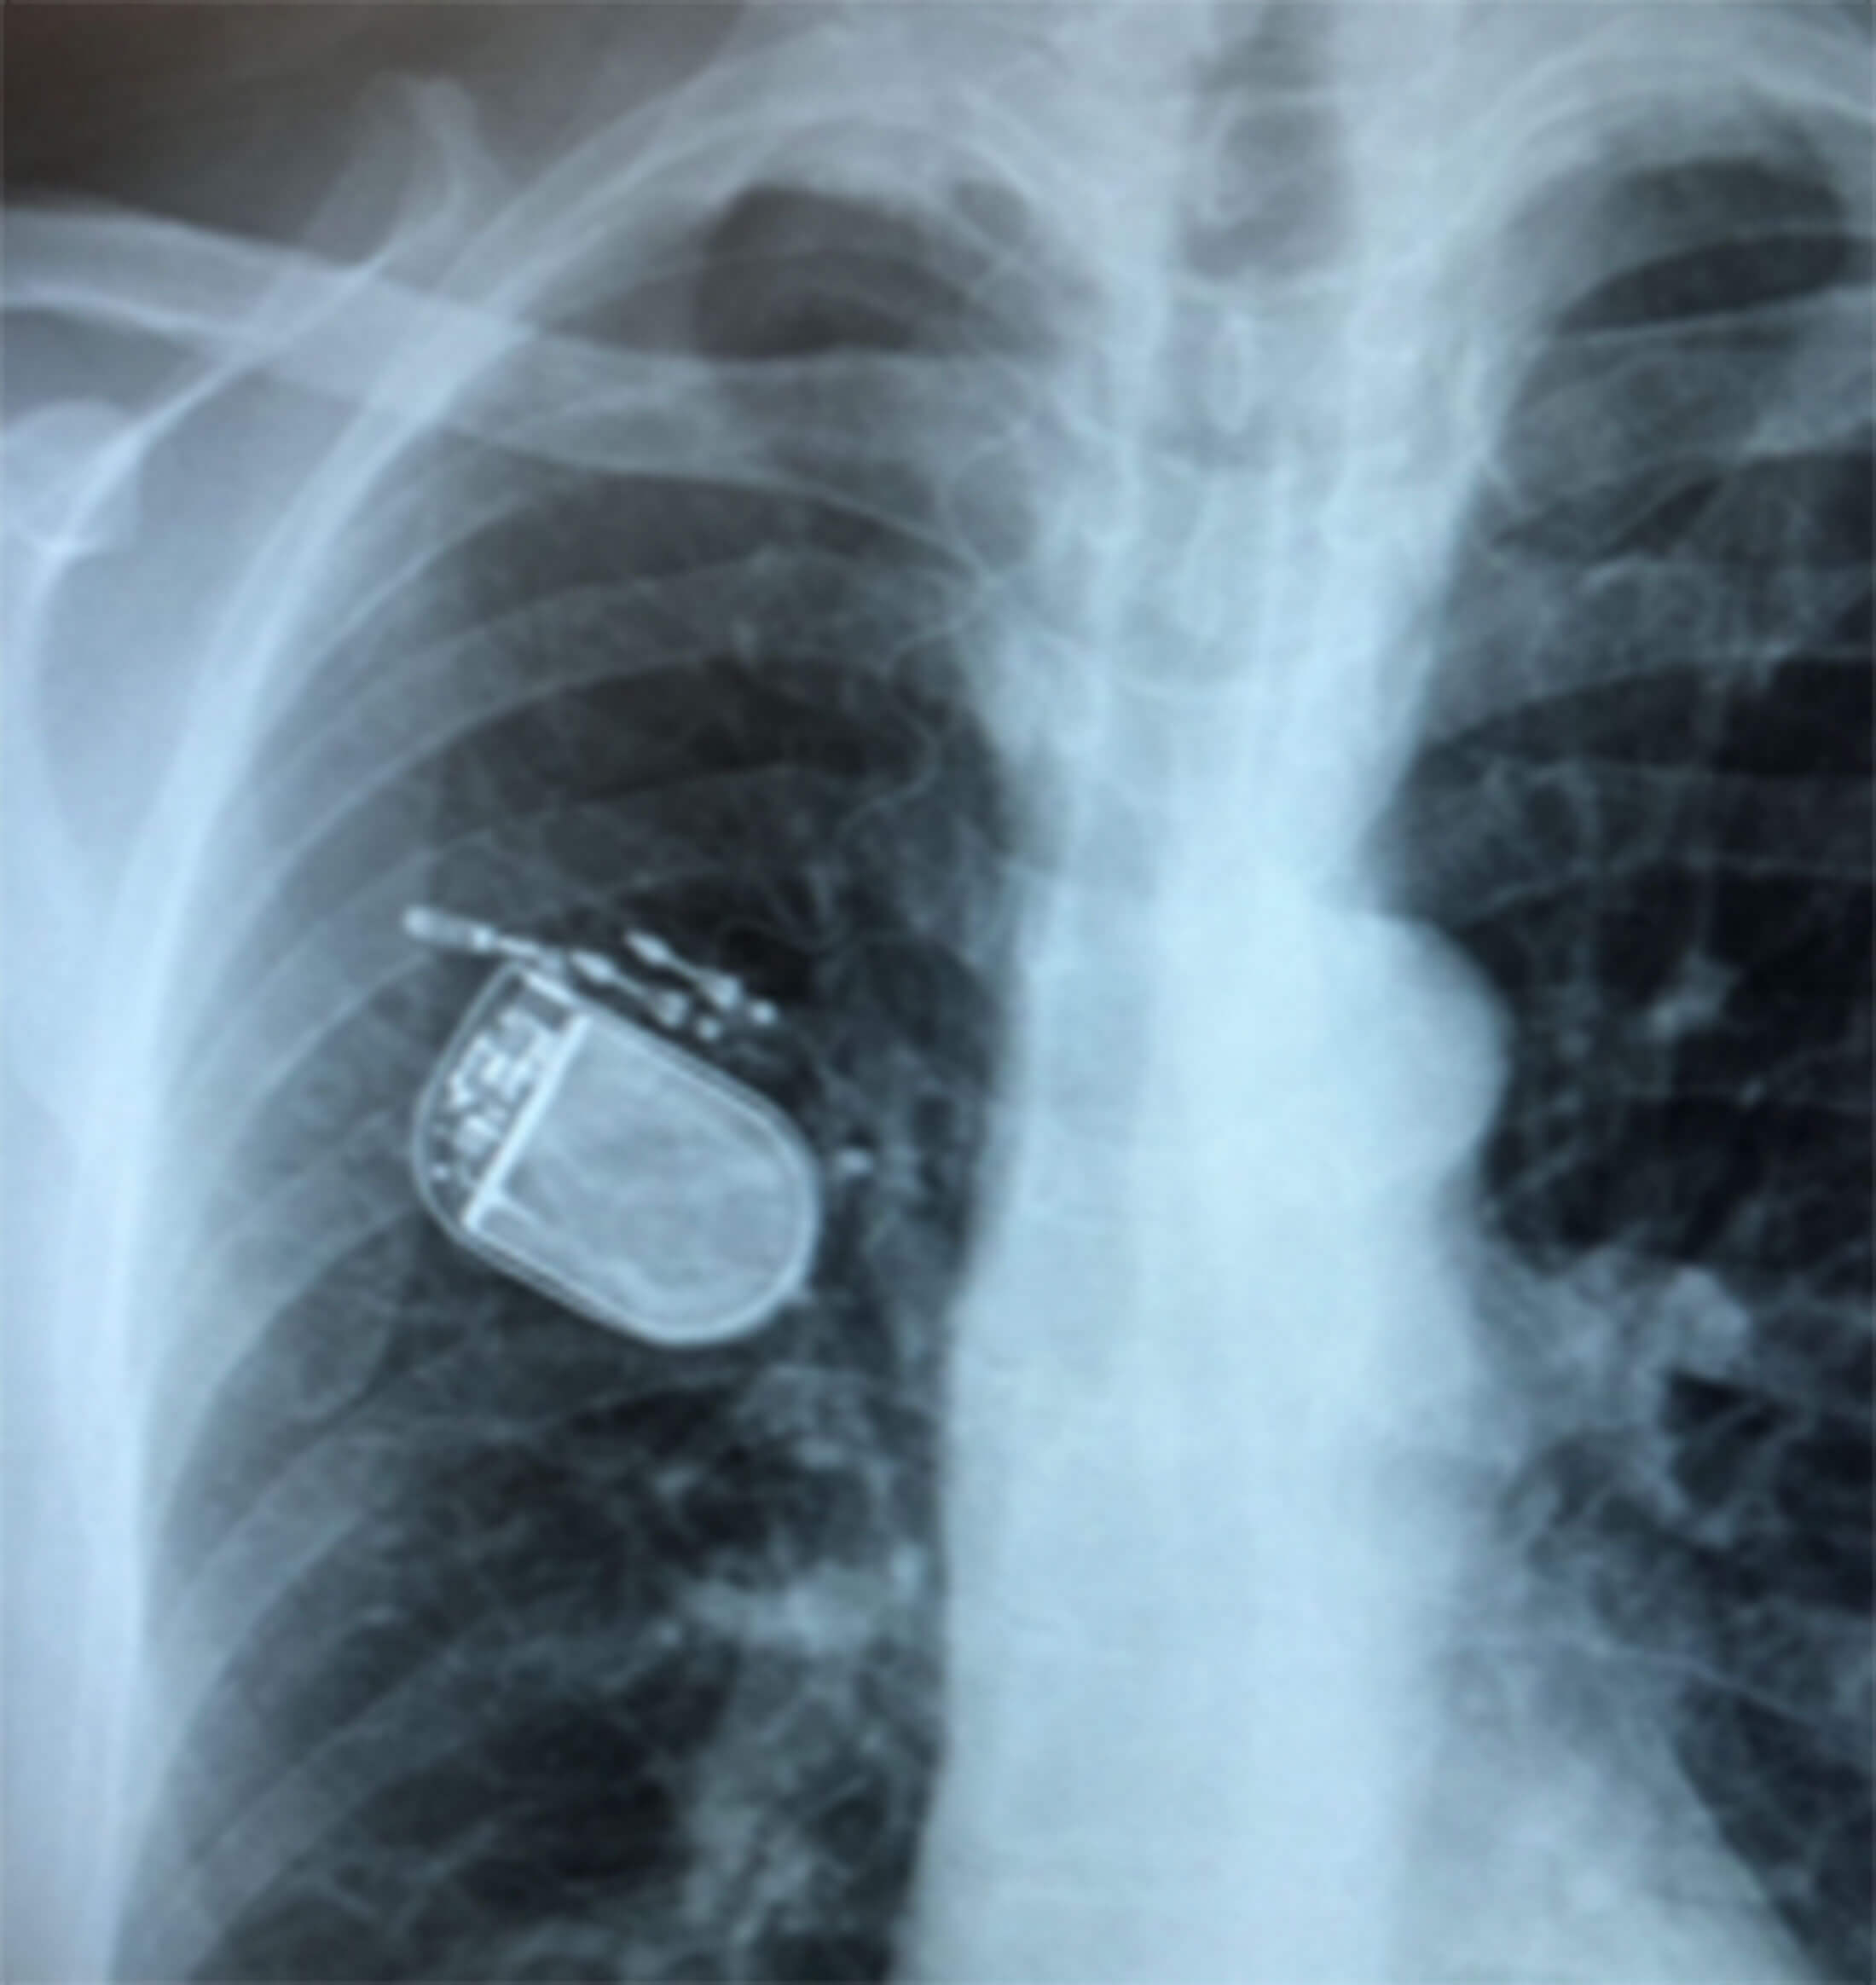

Figure 3b. Postop chest X-Ray showing the pulse generator in situ.